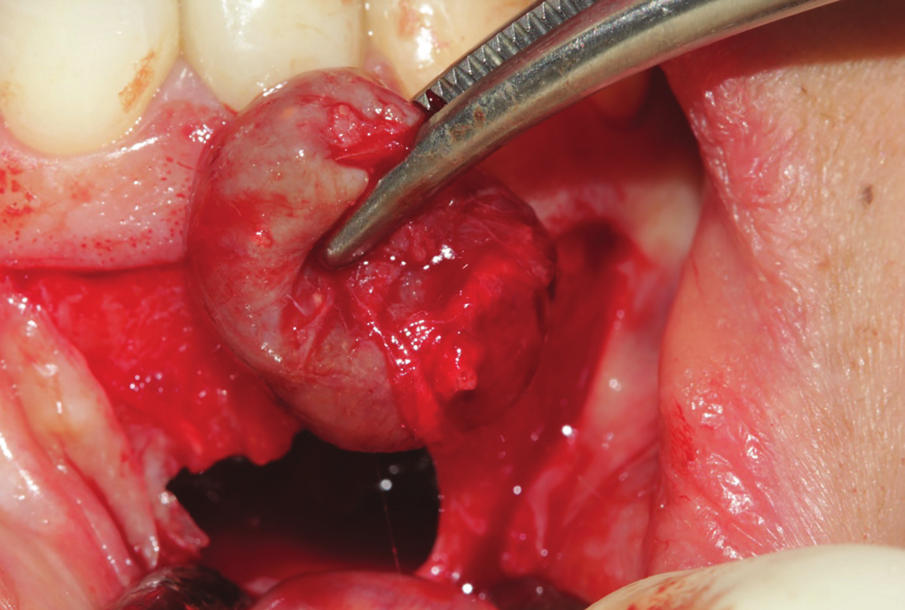

Figure 22: Inter operative view after reflection of mucoperiosteal flap, showing the extended amount of bone loss with intralesional secretion bulging outside the bone cavity.

Figure 23: Enucleation of the 1.5 cm lesion followed by extraction of endodontically perforated tooth no 7.

A 38 years-old female patient came to our clinic with swelling upper anterior area, she was medically fit with no health problems. The patient underwent an orthodontic treatment for 2 years and was about to remove it and place retainer. Intraoral examination showed swelling apical area of tooth no 7. The periapical x-ray and CAT view revealed a lateral perforation on the same mentioned tooth with a well circumscribed radiolucency in apical area (Fig.20, 21). Pain on percussion and slight mobility were noted. A surgical enucleation and extraction of tooth no 7 were conducted (Fig.22, 23, 24). 3 months postoperative CAT view shows an advanced horizontal bone loss with no recurrence of lesion in the area (Fig. 26), clinically after reflection of mucoperiosteal flap, the situation confirmed the CAT image (Fig.25) , the case was planned for PRF -associated bovine bone technique replacing the aggressive autologous bone graft procedure. After collection of PRF from patient blood culture, a first layer of L-PRF covering the bovine bone associated PRF complex (sticky bone) was done (Fig.27). The second layer of L-PRF came to cover the cross-linked collagen membrane (Fig. 28).